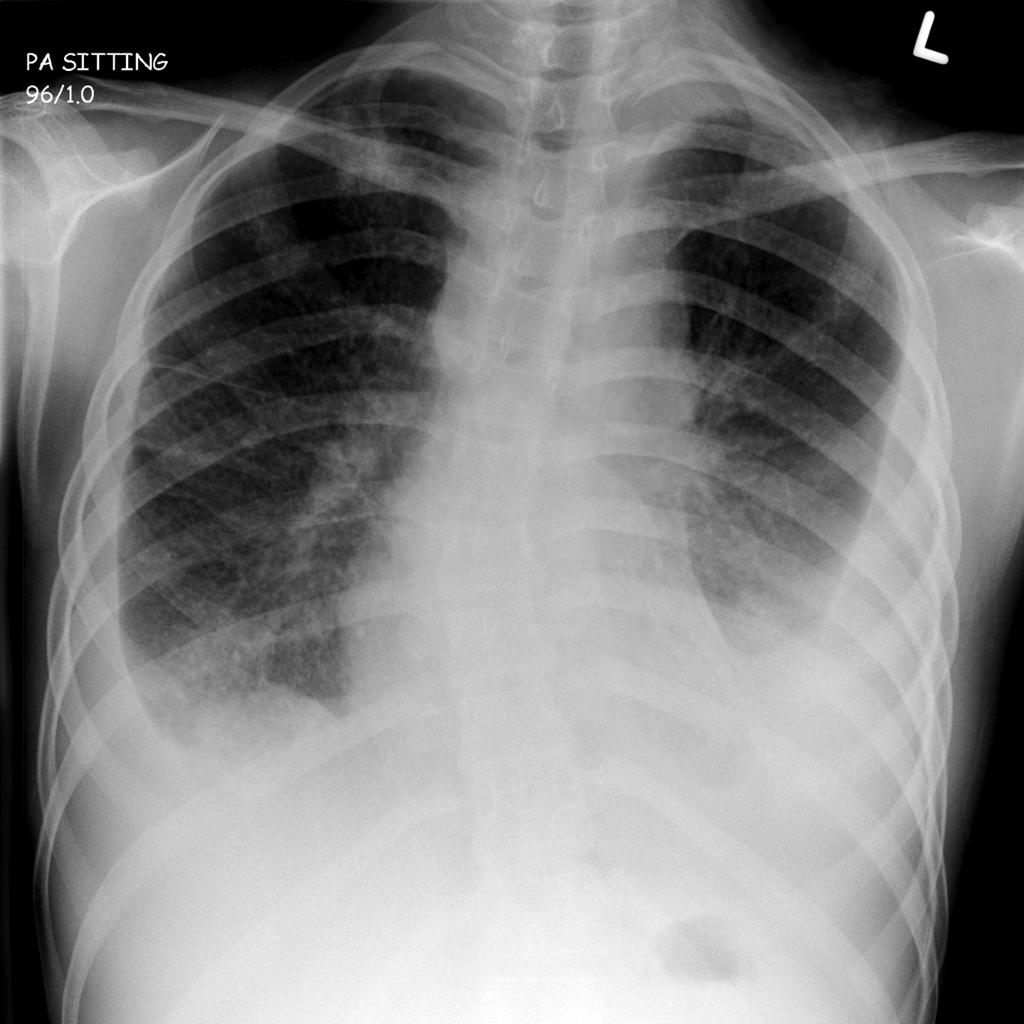

Довольно часто туберкулез на раннем этапе развития становится рентгенологической находкой при очередном прохождении флюорографии при профосмотре.

image

Ограниченный туберкулезный процесс в верхней доле правого легкого

В целом, в начале заболевания состояние заболевших детей и взрослых будет будет мало отличаться от здорового человека. Единственное обследование при данных формах туберкулеза, которое действительно способствует раннему обнаружению туберкулеза легких — это флюорографическое обследование (а еще лучше обзорная рентгенография органов грудной клетки). Именно поэтому флюорография легких входит во все медосмотры и профосмотры.